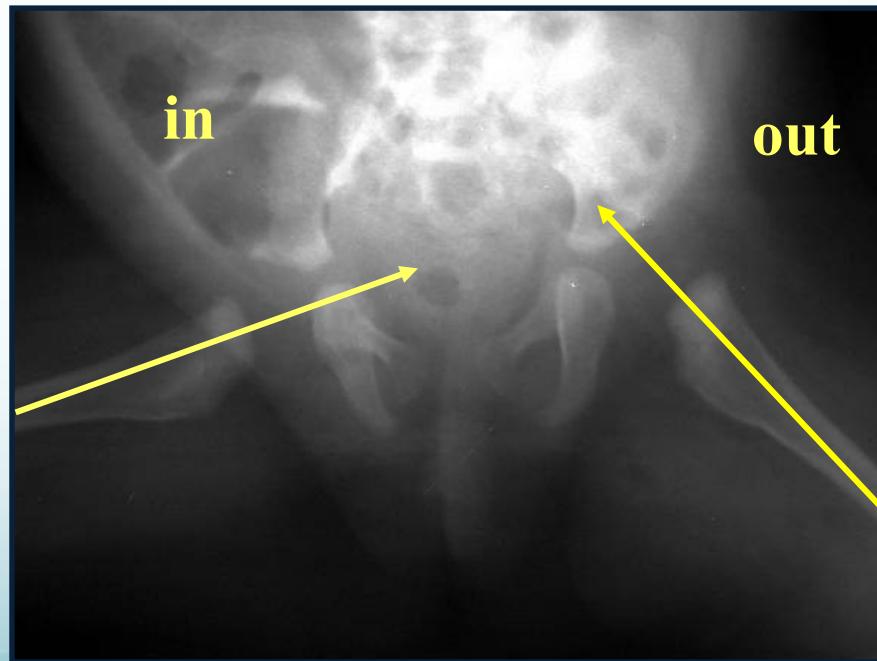

6-12 months of age

- Closed reduction & hip spica cast

- Arthrography-guided

Above 2 years of age

- Surgery

- Open reduction & Acetabuloplasty & Femoral shortening